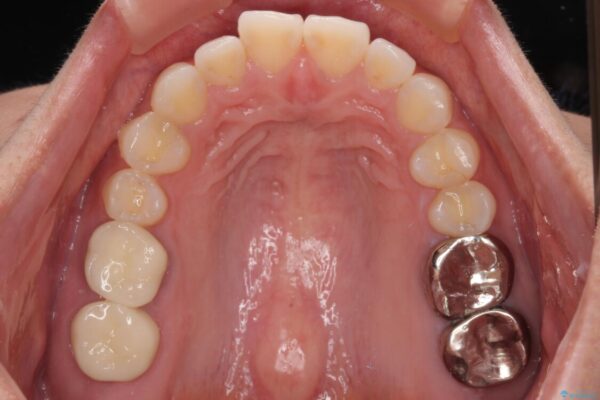

しかし、噛み合わせの相手である右上の第二大臼歯が、長期間噛み合う歯がなかった影響で**挺出(歯が下に伸びてくる状態)してしまっており、このままではインプラントを埋入して被せもの(上部構造)を入れるためのスペースが不足している状態でした。

治療前

• 挺出歯を圧下してスペースを確保!目立たない部分矯正で下顎大臼歯にインプラント治療を実現 治療前画像